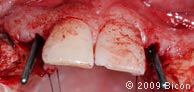

8. Штифты параллельности, показывающие положение и направление остеотомии.

21. Установка направляющих штифтов 3,0 мм внутрь имплантатов.